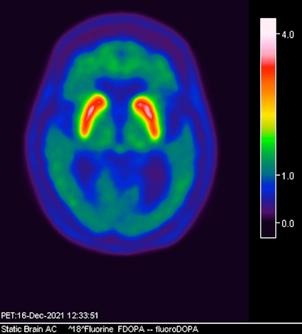

Figura 3. Reconstrucción mediante imagen molecular de imagen híbrida PET-RM 3T con 6-[18F] FDOPA observando disminución de la captación del radiotrazador a nivel de ambos putámenes en la región posterior, media y anterior así como en ambos núcleos ca dados de predominio derecho.

Figura 4. Reconstrucción mediante imagen molecular de imagen híbrida PET-RM 3T con 6-[18F]FDOPA observando captación adecuada y conservada del radiotrazador en el cuerpo estriado (ambos putámenes y núcleos caudados) en un paciente negativo para enfermedad de parkinson.

En cuanto al campo de los estudios de imagen convencional y de laboratorio no existe alguna prueba que pueda confirmar la enfermedad. Sin embargo, las imágenes de diagnóstico por métodos de imagen molecular del tipo no invasivas, como la tomografía por emisión de positrones (PET) en conjunto con un resonador de 3 tesla (RM 3T), pueden respaldar el diagnóstico de un médico, actualmente éste método tiene una sensibilidad diagnóstica de 95.4%, especificidad 100%, valor predictivo positivo del 100% y valor predictivo negativo del 87.5%. (5,6)

La enfermedad de parkinson es una enfermedad neurodegenerativa con afectación principalmente motora (temblor, rigidez y acinesia) de sospecha y diagnóstico clínico, ante la limitación de los estudios de laboratorio y métodos de imagen convencional para el diagnóstico toman gran relevancia las técnicas de imagen molecular no invasivas como el PET-RM y PET-CT con 6-[18F]FDOPA que cuentan con gran sensibilidad y especificidad para respaldar o descartar el diagnóstico médico ante la sospecha de la enfermedad de parkinson y algunas otras enfermedades del trastorno del movimiento.